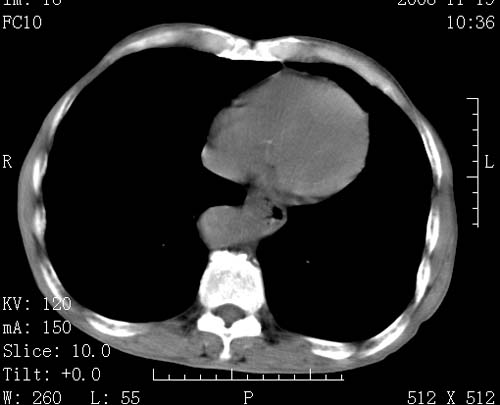

标题: CT16691:m 67 胃镜确诊食管下段及贲门癌 [打印本页]

标题: CT16691:m 67 胃镜确诊食管下段及贲门癌

术前查体,双肺部结节是转移?结核?请点评

1)符合食管癌表现。2)两肺及纵隔淋巴结多发性转移瘤。3)左肺上叶舌段及两肺下叶炎症感染。

食管癌伴双肺转移,评述:肺部毛细血管网丰富,全身血液均快速流经肺部,癌细胞容易过滤定植,形成转移瘤,影象特点为以毛细血管末梢为中心的结节灶,边缘光滑锐利,少见有中心空洞着,不同来源的转移瘤可有各自特点,如甲状腺癌为双肺弥漫性微结节,本例有原发灶,双肺影象灶典型,左肺舌段条带状网格样伴胸膜天幕征,可视为癌性淋巴管炎。